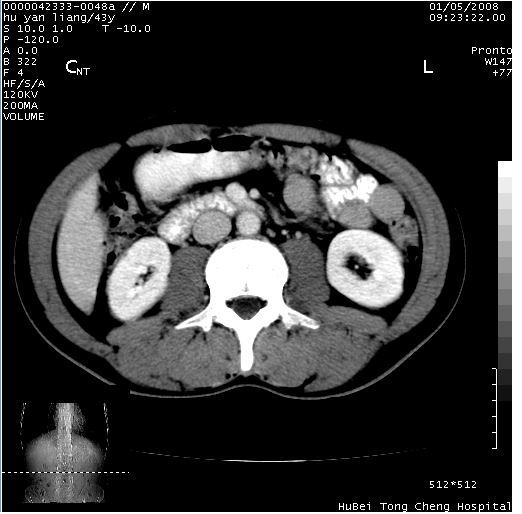

患者 男,43岁。右上腹不适1年余。既往有“肝右叶肝脓肿”病史,经保守治疗后痊愈。

b超提示:1)肝右叶肝内胆管结石。2)肝右叶占位性病变待排。

上中腹部ct轴位平扫+增强扫描(层厚10mm,螺距1.0,重建间隔10mm),图像如下:

肝右叶后段团块状钙化灶,结合病史考虑肝脓肿痊愈后表现。